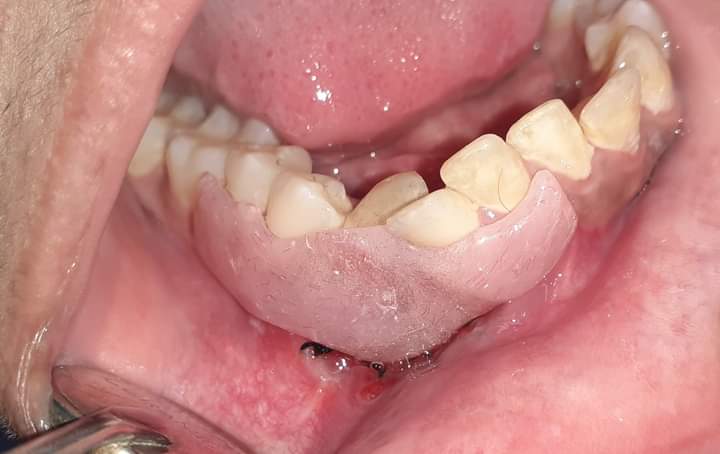

وقال الدكتور سمير حلاوة، إن حجم الكيس كان كبيرًا وممتدًا بعدة تكيسات من منتصف الفك السفلي إلى الجهتين اليمنى واليسرى، حتى منطقة النواجز (premolars)، مما تسبب في إزاحة جذور الأسنان المحيطة، وكان التحدي هو المحافظة على عظام الفك دون الاضطرار لاستئصالها وتعويضها بشريحة معدنية، والحفاظ على الأسنان والضروس المتأثرة.

وأضاف “كان التعاون بين فريق الجراحة وفريق حشو الجذور (حشو العصب)، الذي قام بحشو عصب جميع الأسنان المتأثرة والمحيطة بالكيس، وخلال فترة العلاج تم عمل تسريب وقتي للكيس لتقليل حجمه إلى أصغر صورة ممكنة مع تركيب دعامة أكريلك (obturator) للحفاظ على فتحة التسريب وإمكانية تنظيف وتطهير الفجوة لفترة امتدت أكثر من ستة أشهر، حتى تم استئصال الكيس بنجاح وتحليل أنسجته. وتم ملأ الفراغ العظمي بعظام صناعية مختلطة بعوامل نمو تحفيزية مشتقة من دماء المريضة نفسها تم إعداده داخل الوحدة”.